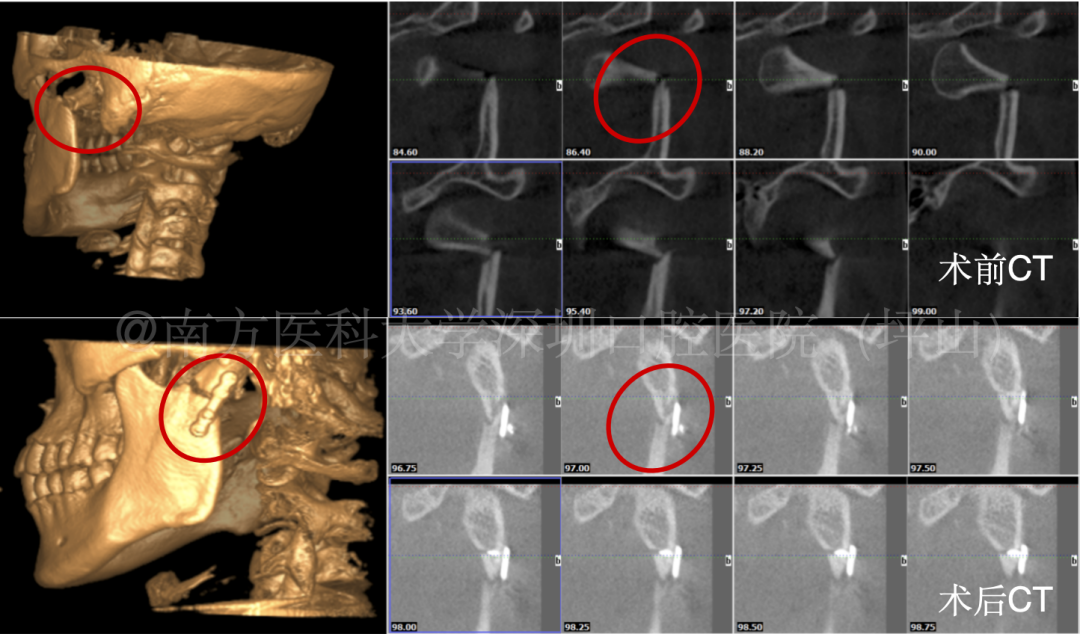

一周前,15 岁的小林在骑自行车时不慎摔伤,入院做 CT 检查,发现左侧髁状突颈部骨折。

34 岁男子李先生,一周前在家中浴室晕倒,颏部着地,受伤严重,导致四颗牙齿脱出、开口受限,在外院进行松牙固定、清创缝合。之后转来我院,CT检查显示双侧髁状突骨折。

▲髁突骨折手术复位固定

医生介绍,下颌骨骨折的治疗的首要目标是恢复稳定的咬合关系,恢复下颌骨的连续性、弓形和下颌支高度。

如果是无移位骨折,或新鲜且移位不大的线性骨折,可采取手法复位、颌间固定等保守治疗方法;有移位骨折则需手术复位固定,确保骨骼正常愈合。

根据受伤部位的不同,采取的手术方式也不尽相同。有的部位,如下颌角部和颏部骨折,可以在口腔内切口完成手术,外表不留瘢痕。

如果是髁突高位骨折,需在耳屏前做切口进行复位固定,专业医生会采取“美容缝合”的方式,用细针细线进行精细缝合,尽量减少瘢痕的形成和对面容的影响,愈合后伤口隐蔽。